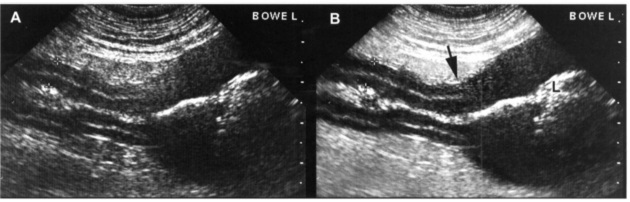

Лимфома ЖКТ поражает как часть стенки кишечника (Рис 1), вызывая локальное утолщение с потерей слоистости, так и целый одел ЖКТ на обширном протяжении без изменения слоев стенки (Рис 2).

РИС 2. Лимфома кишечника у кошки без нарушения структуры органа. А. Иногда у кошек при лимфоме не наблюдается полной потери визуализации слоев стенки кишечника, как, например, у этого 10-летнего животного. На изображении можно видеть диффузные, несколько утолщенные петли кишечника (4 мм). Особенно выражен мышечный слой. В. Meзентериальные лимфатические узлы увеличены умеренно (до 2,2 см в диаметре) (показаны треугольниками)